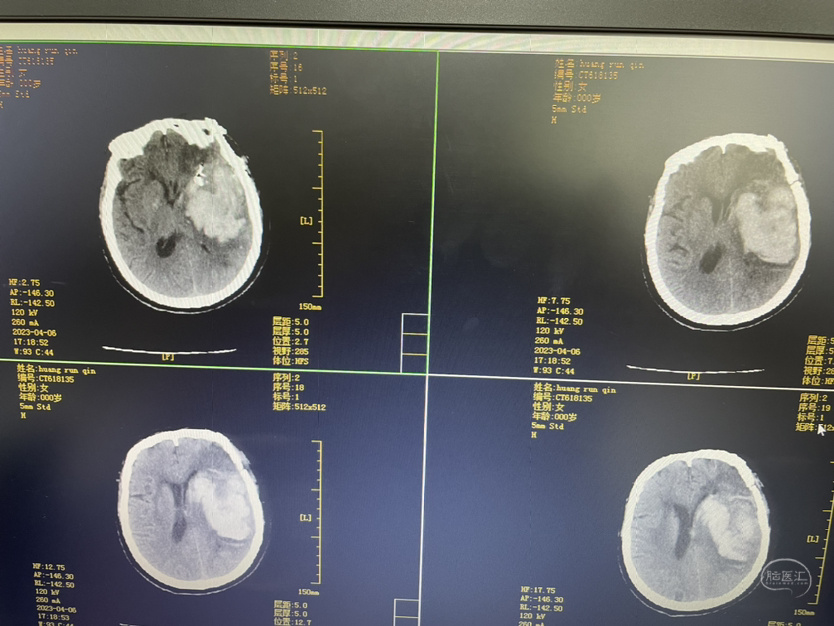

夹闭术后两个月,出院后一个月!再次出血,血肿量大,患者清醒!转上级市级医院,拟予介入栓塞后清除血肿

家属选择保守治疗,患者一直清醒!两个月前在华西行介入栓塞术,血肿吸收!

介入栓塞术后两个月来复查!患者清醒轮椅而来,言语稍含糊,右侧下肢肌力可大于三级,上肢一级!